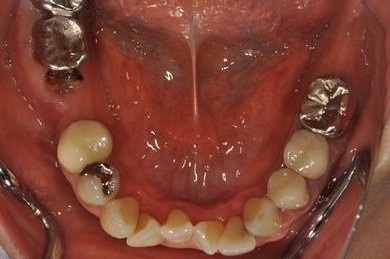

抜歯即日スピードインプラント+セラミック治療

| 治療内容 | インプラント2本(抜歯即日スピードインプラント)、ハイブリッドセラミッククラウン5本(セラミック用土台2本)、ハイブリッドセラミックインレー1本 | ||||||||||||||||||||||||||||||||